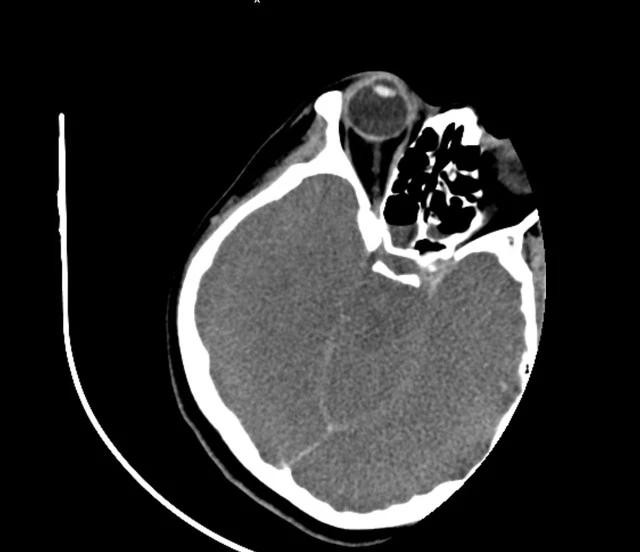

![]() |

| Phim chụp não nữ bệnh nhân bị tổn thương, phù nề sau khi uống nhầm nước đun từ rễ cây lá ngón. TRUNG TÂM CHỐNG ĐỘC |